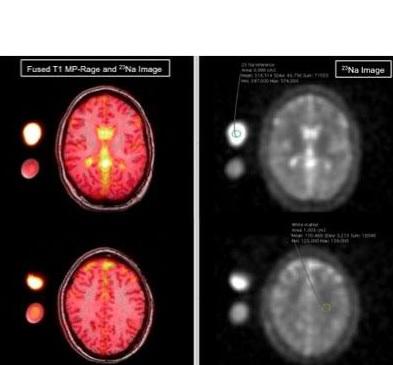

Plus de sel dans le LCR : l’équipe utilise ici une technique d’imagerie par résonance magnétique particulière appelée IRM cérébrale du sodium qui visualise le sodium et confirme que le sodium joue un rôle important dans la chimie du cerveau. L’IRM du sodium montre que chez 12 femmes, âgées en moyenne de 34 ans, diagnostiquées avec migraine et ayant renseigné par questionnaire les caractéristiques de leurs crises (durée, intensité, fréquence, auras…) vs 12 femmes témoins en bonne santé appariées pour l’âge et exemptes de migraines, que :

- les concentrations en sodium des patientes migraineuses sont plus élevées dans le liquide céphalorachidien ;

- en revanche, aucune différence statistique n’est identifiée entre les deux groupes pour les concentrations en sodium dans la matière grise et blanche, le tronc cérébral et le cervelet.